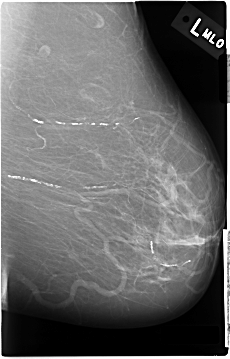

C_0031_1.RIGHT_MLO

LEFT_MLO LINES 4656 PIXELS_PER_LINE 2984 BITS_PER_PIXEL 12 RESOLUTION 50 NON_OVERLAY